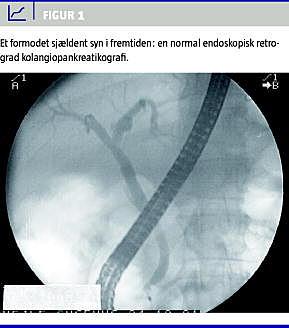

Ved den initiale diagnostik og behandling af patienter med akut pankreatitis er det vigtigt at skelne mellem de pankreatitistilfælde, der er udløst af galdesten, og de tilfælde, der er udløst af alle andre årsager, idet man ved førstnævnte har muligheden for at fjerne den udløsende faktor; nemlig den/de sten i de dybe galdeveje, der har blokeret udløbet fra papilla vateri til duodenum. Som primær undersøgelse til skelnen mellem galdestensudløst akut pankreatitis (GAP) og de øvrige tilfælde anbefales ekstern ultralydskanning over abdomen, idet denne undersøgelse har høj sensitivitet og specificitet for galdeblæresten [1]. Hos de patienter, hvor det drejer sig om GAP, har der været megen diskussion om, hvornår man efterfølgende har skullet udføre ERCP (Figur 1 ), idet man i forbindelse med denne undersøgelse kan udføre endoskopisk stenekstraktion og dermed fjerne den udløsende årsag, men samtidigt kan risikere, at pankreatitis forværres. Formålet med denne statusartikel er at formidle opdateret viden på området.